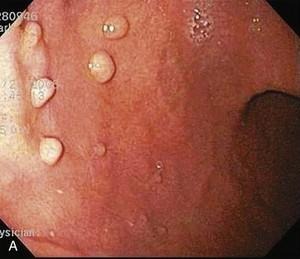

胃底腺ポリープは周囲の胃粘膜と同じ色調、模様をしている2-3mm大の小さなポリープで、胃穹窿部から胃体部、特に大弯側に複数みられることを特徴としています。ヘリコバクター・ピロリ陰性のきれいな胃にしか発生しないことから、胃底腺ポリープが認められた胃は、胃がんのリスクが低いと考えられます。

ヘリコバクター・ピロリ菌陰性者が増加しており、胃内鏡検査で偶然発見される機会も増加しています。

女性に多くみられ、女性ホルモンなどの関与の指摘もされていますが、はっきりした原因は不明です。胃食道逆流症(GERD)などでプロトンポンプ阻害薬を長期間服用するとポリープが増大し数が増加すると考えられています。ほとんどの方は経過観察していくとポリープの数は増えていく事が多くみられます。

胃底腺ポリープは基本的に経過観察で問題ありません。ほとんどの胃底腺ポリープは内視鏡治療を含めた切除の必要はありません。

胃底腺ポリープの中で、徐々に大きくなる場合、赤みが強くなる場合に、ごく稀に胃底腺型胃がんを生じることがあるので、胃底腺ポリープは100%安心というわけではありません。